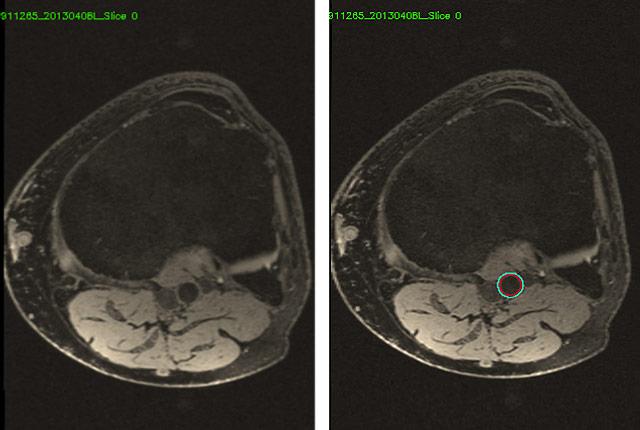

He is principal investigator in a massive study to establish a computer algorithm’s ability to identify an artery and delineate its inner and outer boundaries, just as radiologists do by hand to discern vessel wall thickening.

Knee MRIs, of course, are not intended to diagnose atherosclerosis, but rather to reveal sources of musculoskeletal pain. These patient scans had initially been ordered in a study of osteoarthritis. But knee MRIs inevitably include the popliteal artery, which runs vertically behind the knee joint. It has the potential to depict someone’s vascular health as well as vessels nearer the heart.

AI’s magic lies in its speed and consistency. It would be unthinkable for a radiologist to hand-label 3.5 million blood vessels and contours. It only took seven minutes for AI to process one knee scan, versus up to three hours for an experienced human. (One MRI knee series comprises about 70 images, collectively covering about 4 vertical inches of knee joint.)